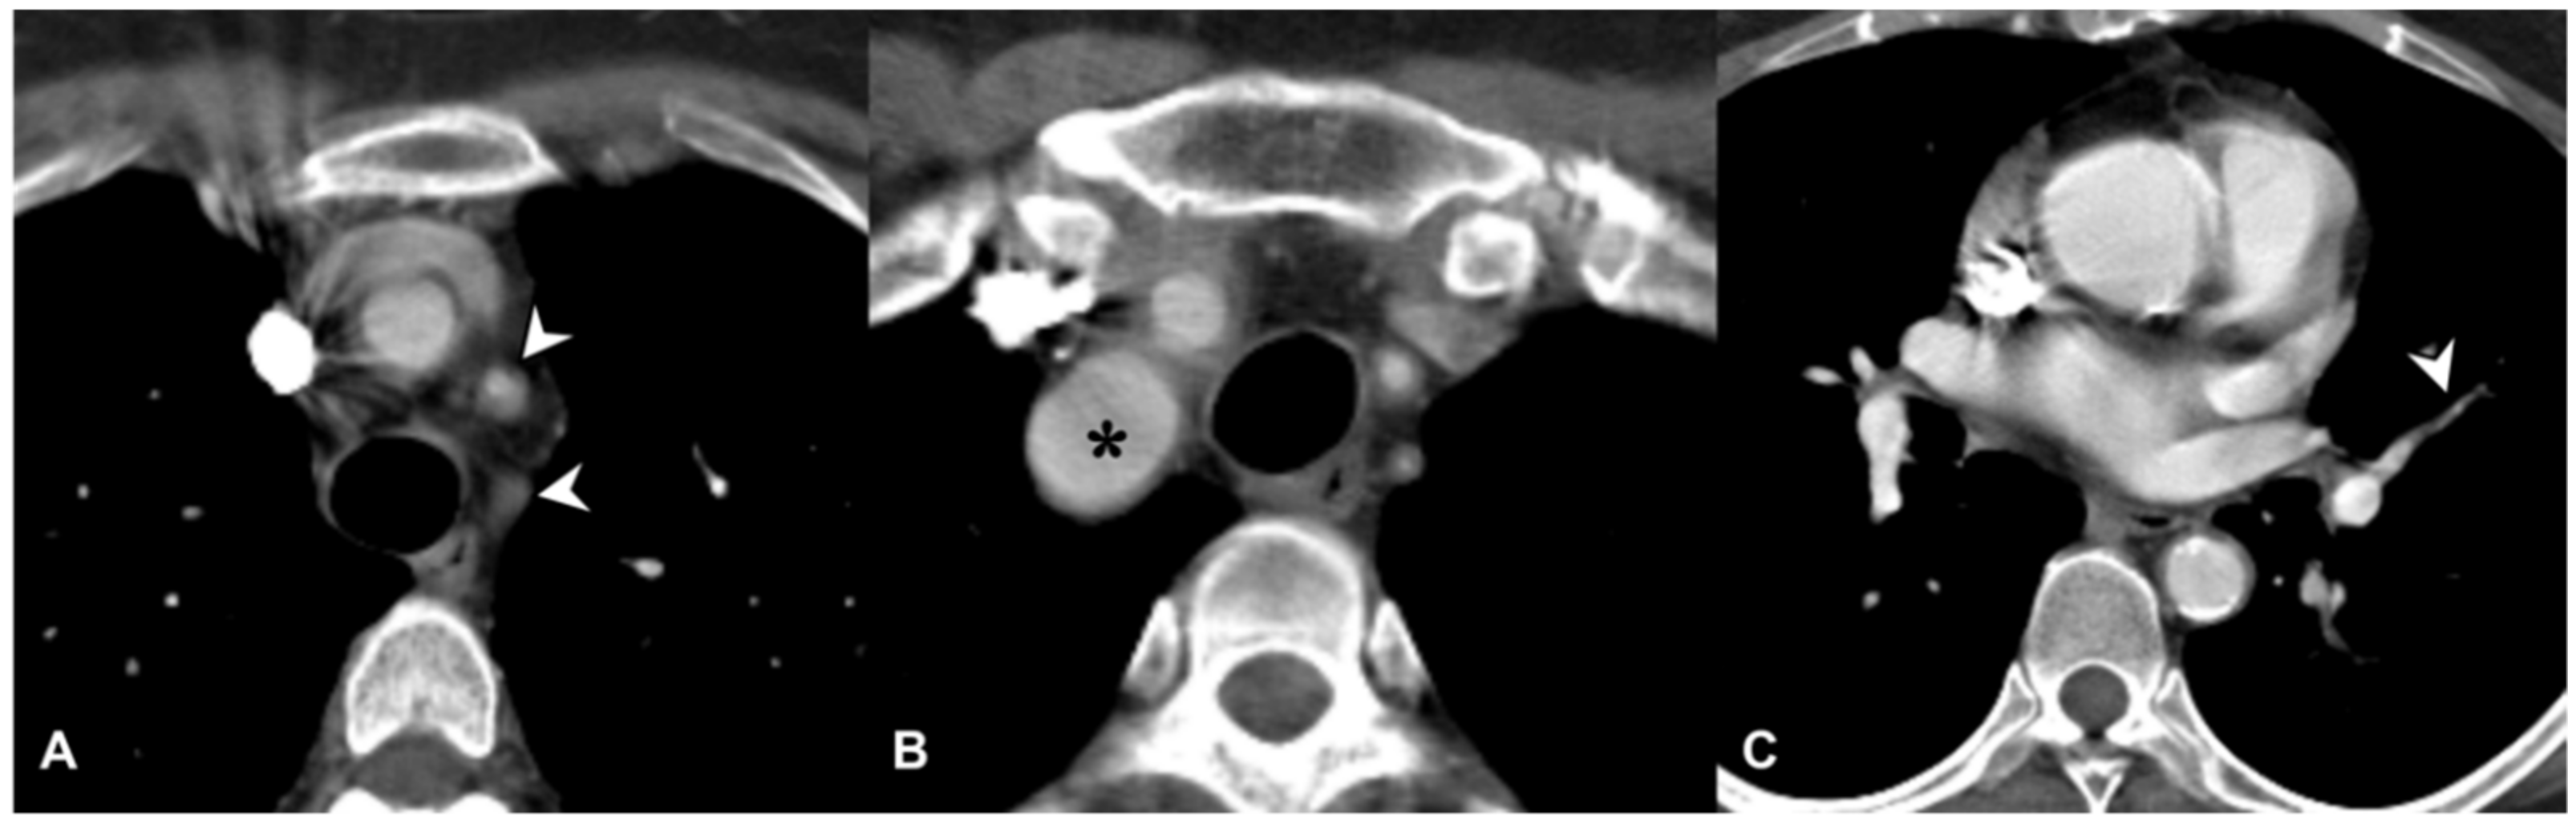

2.8. Variable Vessel Vasculitis (VVV)

| Bechet’s disease | Subpleural alveolar infiltrates and wedge-shaped or ill-defined rounded areas with increased opacity, pulmonary artery aneurism |